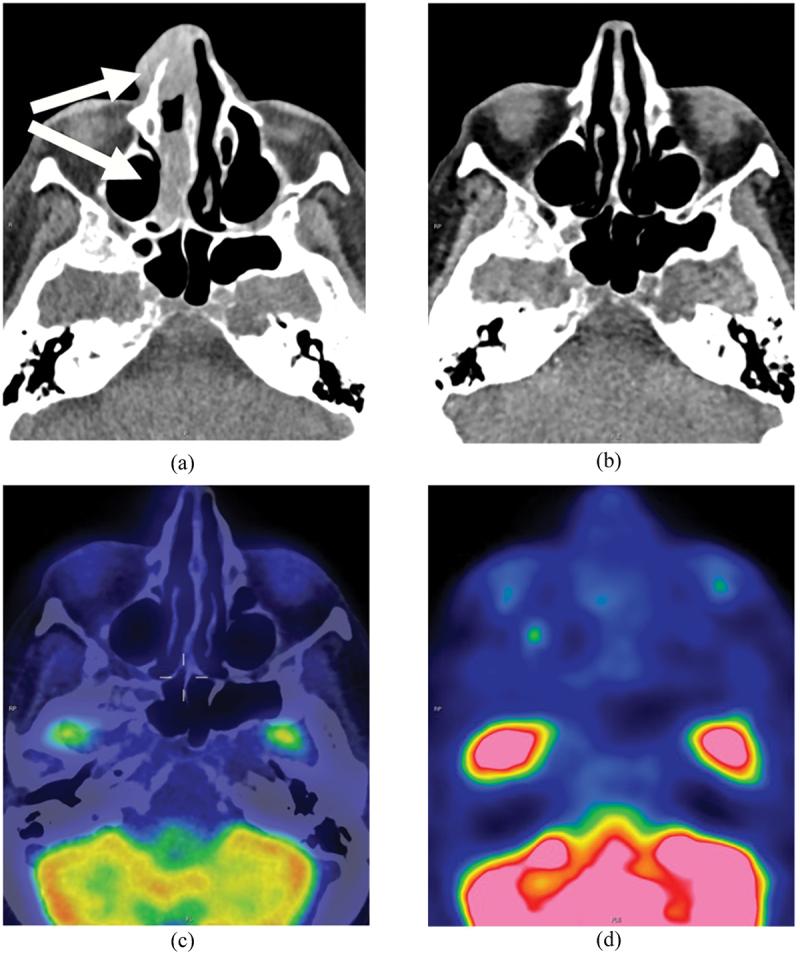

Methotrexate is a commonly employed folate antagonist used as a disease modifying antirheumatic drug. It is recommended by the European League Against Rheumatism Guidelines as an add-on therapy for the treatment of polymyalgia rheumatica. Lymphoproliferative disease developing during methotrexate treatment is recognised as methotrexate-associated lymphoproliferative disorder. We describe a patient with polymyalgia rheumatica on long-term methotrexate treatment presenting with double vision and systemic symptoms concerning for giant cell arteritis. Two months prior, she had noticed a mass of the right nasal dorsum. Neuroimaging showed several lesions of the nasal cavity and a clival lesion. Nasal cavity biopsy revealed diffuse large B-cell lymphoma, and FDG-PET/CT 3 weeks after methotrexate cessation showed significant interval disease regression, confirming the diagnosis of methotrexate-associated lymphoproliferative disorder. Follow-up FDG-PET/CT 4 months after methotrexate cessation showed complete radiological regression of lymphoproliferative lesions. The cumulative incidence of methotrexate-associated lymphoproliferative disorder in patients with rheumatoid arthritis treated with methotrexate has been reported to be up to 4.7% at 10 years in a retrospective study. Cessation of methotrexate resulted in spontaneous regression in 59% of patients. It is important to include methotrexate-associated lymphoproliferative disorder on the differential diagnosis for patients on long-term methotrexate treatment who present with neuro-ophthalmic symptoms and signs as tissue diagnosis prior to commencing steroid treatment is essential to secure the diagnosis and guide treatment.

甲氨蝶呤是一种常用的叶酸拮抗剂,用作改善病情抗风湿药。欧洲抗风湿病联盟指南推荐其作为治疗巨细胞动脉炎的附加疗法。在甲氨蝶呤治疗期间发生的淋巴增殖性疾病被认为是甲氨蝶呤相关淋巴增殖性疾病。我们描述了一名长期接受甲氨蝶呤治疗的巨细胞动脉炎患者,出现复视和全身症状。两个月前,她注意到右鼻背有一个肿块。神经影像学检查显示鼻腔有多处病变以及一个斜坡病变。鼻腔活检显示为弥漫性大B细胞淋巴瘤,停用甲氨蝶呤3周后的FDG-PET/CT显示病情有显著的间隔期消退,证实了甲氨蝶呤相关淋巴增殖性疾病的诊断。停用甲氨蝶呤4个月后的随访FDG-PET/CT显示淋巴增殖性病变完全影像学消退。一项回顾性研究报告称,接受甲氨蝶呤治疗的类风湿关节炎患者中甲氨蝶呤相关淋巴增殖性疾病的累积发病率在10年时高达4.7%。停用甲氨蝶呤后,59%的患者病情自发缓解。对于长期接受甲氨蝶呤治疗且出现神经眼科症状和体征的患者,在鉴别诊断中纳入甲氨蝶呤相关淋巴增殖性疾病很重要;因为在开始使用类固醇治疗之前进行组织诊断对于确诊和指导治疗至关重要。